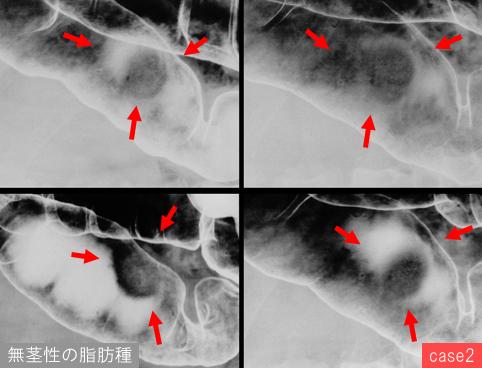

疾病(病理主体)的分类其它/

部位(按器官分)大肠/横结肠

检查方法X线

肿瘤最大直径25~29